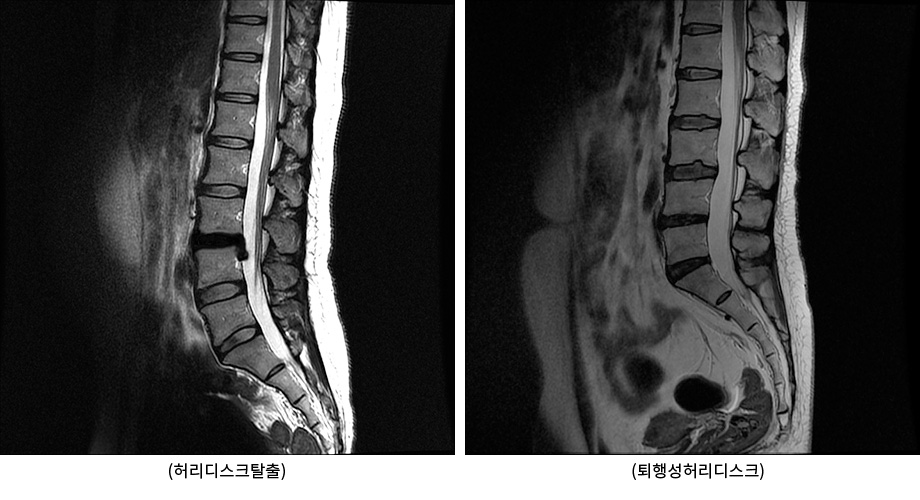

서울대 재활의학과 교수님이 쓴 책의 내용인데 1주일에 20km 이상을 달리는 사람과 운동은 하지 않는 사람들을 비교해 봤을 때, MRI 영상에서 달리기를 꾸준히 하는 사람들이 허리디스크가 두꺼웠고 그 속의 수분 함유하고 있는 분량이 높았다는 내용이 있었습니다.